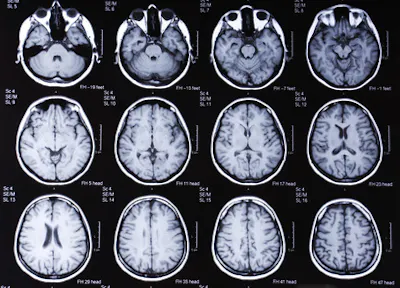

Diagnosticare il morbo di Alzheimer attraverso una semplice scansione cerebrale. Il nuovo metodo, sviluppato dagli scienziati dell'Imperial College di Londra, è stato appena descritto in una pubblicazione sulla rivista Nature Communications Medicine. La tecnica, sviluppata da Eric Aboagye e dal suo team, ha utilizzato la tecnologia di apprendimento automatico che ha permesso agli scienziati di esaminare le caratteristiche strutturali del cervello, inclusa l'analisi di regioni dell'organo che non erano associate all'Alzheimer.

Il nuovo approccio sviluppato dai ricercatori consentirebbe, dunque, di diagnosticare precocemente l'Alzheimer attraverso una semplice risonanza magnetica cerebrale (MRI) eseguita su una macchina standard. Attualmente, non esiste una cura per il morbo di Alzheimer, ma una diagnosi in fase iniziale consentirebbe ai pazienti di avere accesso a un trattamento più precoce e quindi più efficace.